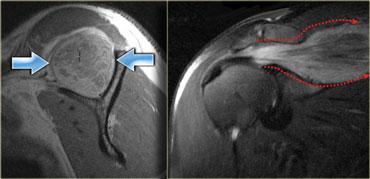

Bên trái là ví dụ về một tổn thương độ cao.

Có sự đứt hoàn toàn của gân hoặc chỗ nối cơ-gân của cơ ngực.

Bệnh nhân này sẽ mất hoàn toàn chức năng của cơ này.

Bên trái là ví dụ về một vết rách ở cơ ngực lớn bên trái.

Trên ảnh T1 có trọng số, có một khoảng hở trong cơ với một lượng nhỏ mỡ lấp đầy vào đó.

Chuỗi xung gradient echo cho thấy sự tích tụ dịch khu trú và một số tăng tín hiệu trong cơ.

Tổn thương trông có vẻ không nghiêm trọng.

Tuy nhiên, khi được yêu cầu co cơ ngực hoàn toàn, có thể thấy rõ sự bất đối xứng do đứt hoàn toàn cơ (mũi tên xanh).

Về mặt lâm sàng, đây là tổn thương độ 3, với mất chức năng hoàn toàn của cơ.